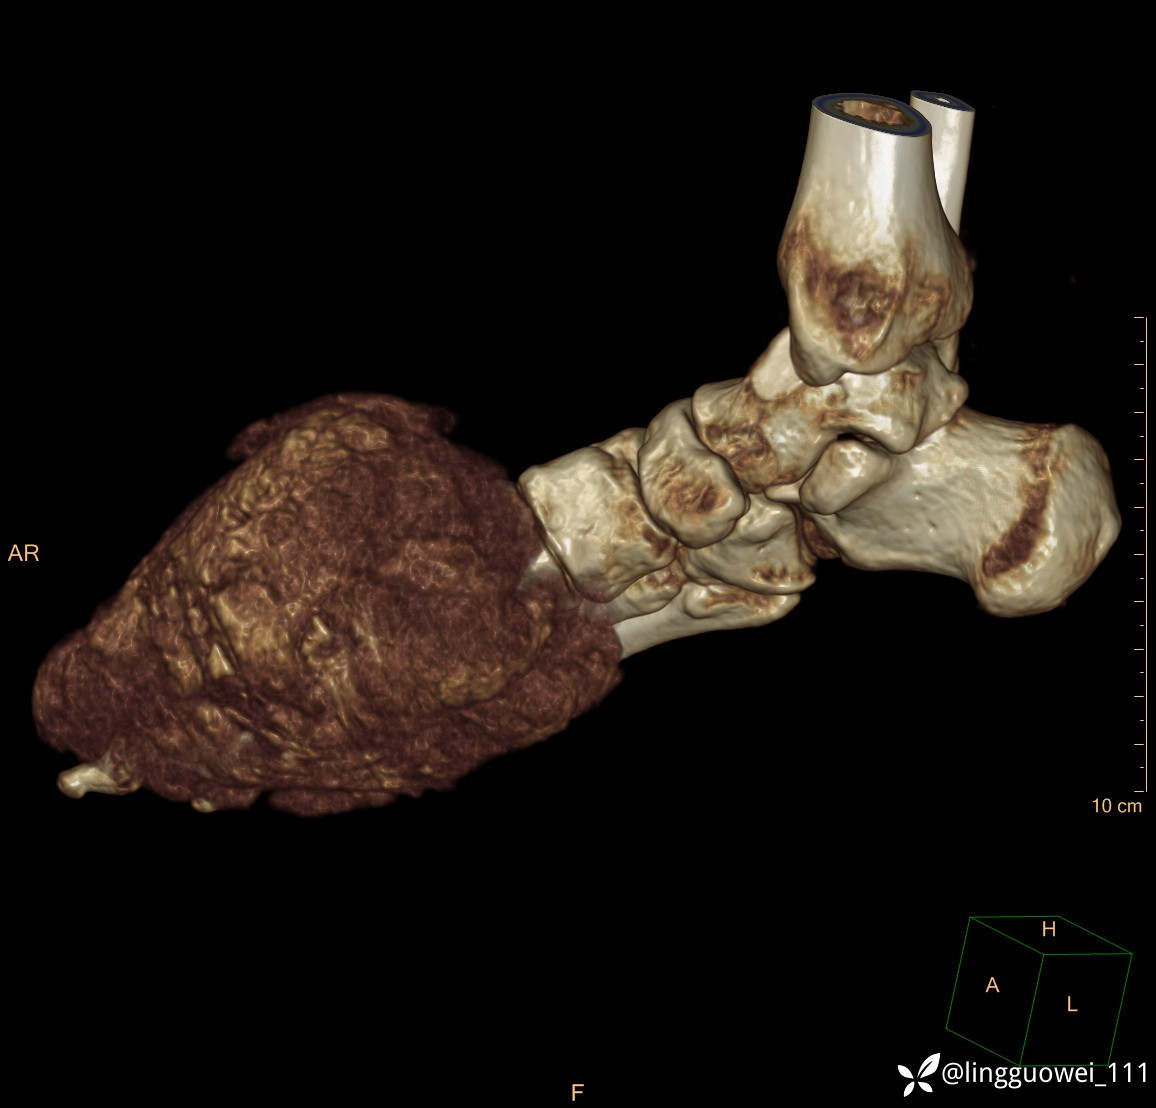

患者于2年余前高嘌呤饮食及大量饮酒后出现全身多处关节痛风石,以右足第一跖趾关节和右手为显,局部红肿热痛反复发作,自行口服药物后可缓解(药物可疑为强的松、双氯芬酸钠等,具体不详)。2年来右足痛风石明显增大,约10cm*5cm*15cm,局部红肿发热,3天前患者再次大量饮酒后痛风石顶部破溃,可见4cm*3cm皮损,较多白色豆渣样分泌物流出,为求进一步治疗来诊,门诊诊断为“右足痛风石破溃伴感染”, 收住院拟手术治疗,患者起病以来,无发热,精神佳、胃纳好、睡眠佳,大小便正常。

专科检查:右足外观畸形,足背部可见巨大痛风石形成,痛风石大小约10cm*5cm*15cm,局部皮肤红肿发热,痛风石顶部破溃,可见4cm*3cm皮损及白色豆渣样分泌物流出;痛风石界限清,质偏硬,局部触及波动感,无压痛,移动度差。右足踇趾及第2趾被痛风石压迫,关节活动受限。肢端血运、感觉无异常。 右手稍肿胀,2-5指背侧可见多发痛风石形成,最大者约花生米大小,皮肤完整未破溃,痛风石界限清,质偏硬,局部触及波动感,无压痛,移动度差。